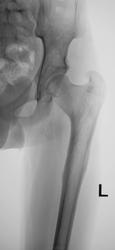

А, вот как было два года тому.

А он, простите, в армию собрался? Или военкомат настаивает? Впадина мелкая, головка и шейка деформированы, шеечно-диафизарный угол явно не 127, куда же ребенку в армию?

Бедное детище, пусть военкомат поплачет по его судьбе. А парень сильно хромает? Ему же жить и жить еще! А второй-то сустав такой же или процесс односторонний? Я к тому, что Пертеса как правило двухсторонний процесс, а если у ребенка поражен один сустав, то не может ли это быть врожденной или ранней детской нелеченной травмой?

Нет "парень" уже приспособился, даже не хромает. Со слов отца (работает у нас плотником) "это" от рождения.